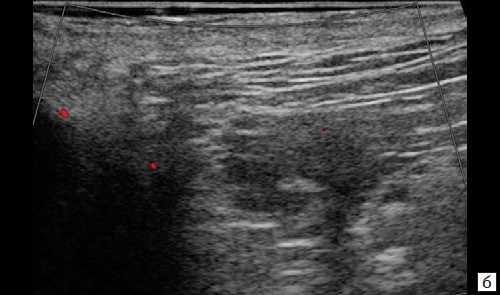

При контрольном УЗ-исследовании: описываемое ранее жидкостное образование в подкожно-жировой клетчатке четко не визуализируется, в его проекции – умеренная неоднородность ткани без четких очаговых изменений (рис. 4, а). Сосудистый рисунок в подкожно-жировой клетчатке в данной проекции не обогащен (рис. 4, б).

Рис. 4. а – В-режим. Через 3 месяца после оперативного вмешательства. Описываемое ранее жидкостное образование со свищевым ходом в подкожно-жировой клетчатке четко не визуализируется, в его проекции – умеренная неоднородность ткани без четких очаговых изменений;

б – режим ЦДК. Через 3 месяца после оперативного вмешательства. Сосудистый рисунок в подкожно-жировой клетчатке в данной проекции не обогащен.